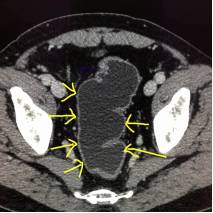

图4

图5

如图4:红色箭头指的就是未做胃肠道准备的患者,可见聚集的直肠明显增厚,这一段肠管很容易被认为是增厚的病变,直肠癌?这时候就要打问号了,是真正的增厚的肠管还是粪便。

这时候再看图5,同一个患者同一个部位,检查前清洁灌肠后,向肛门注入清水,可见直肠被充盈起来了,壁很薄,一点都没有增厚。所以如果单单就图4,很容易被误诊为直肠癌。这也正体现了做CT之前胃肠道准备的重要性。如果临床配合不好,做的不足,会影像CT的诊断结果。

图6

图6:这是图4患者的图像,向肛门注入清水,整个结肠充盈了清水后,壁薄,显示得一览无遗。